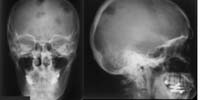

Skelettröntgen (RadioSurf) Interaktive Lernmodule zur Diagnostischen Radiologie des Skeletts für Studierende der Medizin public (öffentlich) Deutsch Studierende 1. Jahr | Studierende 2. Jahr | Studierende 3. Jahr | Studierende 4. Jahr | Studierende 5. Jahr | Studierende 6. Jahr | Ärztinnen/Ärzte in Weiterbildung Tutorial | Quiz | Mustererkennungstraining Website Anatomie

Schädel-CT (RadioSurf) Lernprogramm zu Schädel-CT in Kooperation mit Universitätsklinikum Freiburg i. Br. erstellt. public (öffentlich) Deutsch Studierende 3. Jahr | Studierende 4. Jahr | Studierende 5. Jahr | Studierende 6. Jahr | Ärztinnen/Ärzte in Weiterbildung Mustererkennungstraining Website Radiologie

Thoraxröntgen (RadioSurf) Interaktive Lernmodule zur Diagnostischen Radiologie des Thorax für Studierende der Medizin public (öffentlich) Deutsch Studierende 1. Jahr | Studierende 2. Jahr | Studierende 3. Jahr | Studierende 4. Jahr | Studierende 5. Jahr | Studierende 6. Jahr | Ärztinnen/Ärzte in Weiterbildung Tutorial | Quiz | Mustererkennungstraining Website Anatomie